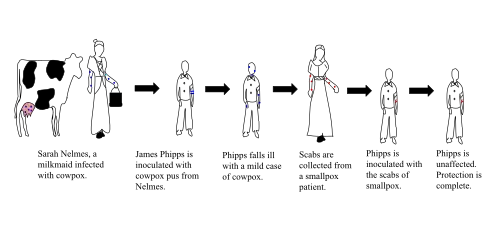

У крестьянки Сары Нелмс (Sarah Nelmes; в одной из неопубликованных рукописей Дженнер называет её Люси[8]), заразившейся коровьей оспой, появились на руке несколько пустул. 14 мая 1796 года их содержимое Дженнер втёр в царапину на теле восьмилетнего Джеймса Фиппса (1788—1853), сына садовника Дженнера. У мальчика появилось лёгкое недомогание, которое прошло через несколько дней. Через полтора месяца Джеймсу Фиппсу была привита натуральная (человеческая) оспа, однако болезнь не развилась. Через несколько месяцев была сделана вторая прививка натуральной оспы, спустя пять лет — третья, с аналогичными результатами.

Джеймса Фиппса нередко называют первым человеком, который был вакцинирован от натуральной оспы прививкой коровьей оспы, но это не соответствует действительности, поскольку до него такой процедуре подверглись несколько человек. Так, в 1791 году учитель из Киля Петер Плетт произвёл такие прививки троим детям; его работа в этом направлении в 1790-е годы (ранее подобных экспериментов Дженнера) долгое время оставалась малоизвестной[9]. Ещё раньше, в 1774 году, применил сходную процедуру к трём членам своей семьи английский фермер из графства Дорсетшир по имени Бенджамин Джести[10]. Однако именно Дженнер в 1798 году издал брошюру с подробным описанием своего исследования, и этот труд стал первым опубликованным отчётом о вакцинации, сделавшим эту практику известной во всём мире.